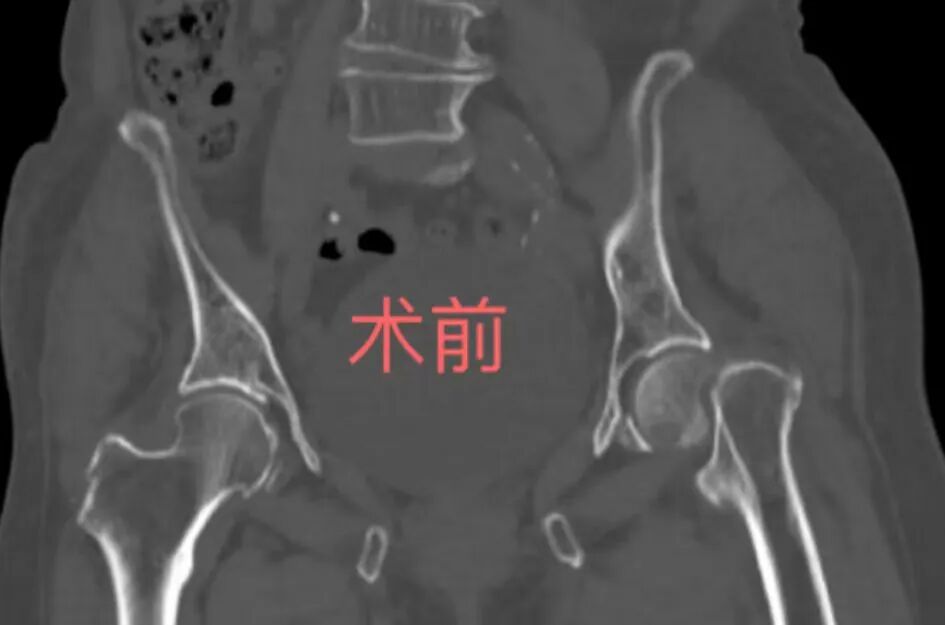

刘主任介绍说,80岁高龄,自身存在一些老年基础疾病,像骨质疏松、高血压、糖尿病,这位老人是一个月前在家活动时不慎摔倒,致左髋部疼痛、活动受限,现左髋部疼痛明显,各向活动受限,不能下地行走,已经严重影响了患者日常生活,经人介绍后,国庆假期来到我院,我们经过详细检查诊断为左侧股骨颈陈旧性骨折。在与老年医学科、麻醉科、手术室等科室专家会诊后,一致认为:患者高龄,左下肢血栓形成,非手术治疗不能改善患者生活质量,若长期卧床,随时可能因内科并发症危及生命,手术虽然风险大,但人工股骨头置换术势在必行。

微信图片_2025-10-11_092719_825.png

隔日,老人顺利进行了人工股骨头置换术,手术在1小时内完成,术中各项生命体征正常,平稳度过危险期。术后在医护人员与家属的精心护理下,第二天老人便坐起进食,三天后便下床行走活动,手术效果较好。